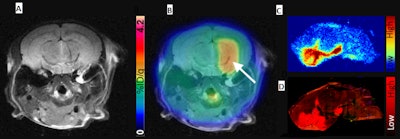

(A) Representative contrast-enhanced T2-weighted MR coronal image of AAV-transduced mouse brain. (B) Corresponding merged F-18 DASA-23 PET/MR images (10 to 30 minutes summed F-18 DASA-23 activity). The white arrow indicates regions of radiotracer uptake corresponding to the transduced region. (C) Autoradiography of mouse brain sections excised one hour after radiotracer administration and (D) an immunofluorescence stain for PKM2. Image courtesy of Thomas Haywood, PhD, et al and Stanford University School of Medicine.PKM2 has the potential to be further developed into a PET reporter gene system for the imaging of gene therapy in the CNS, the researchers concluded. In addition to testing in mice, the radiotracer has also recently been used at Stanford in the first human trials for the early detection of a therapeutic response in glioblastoma.